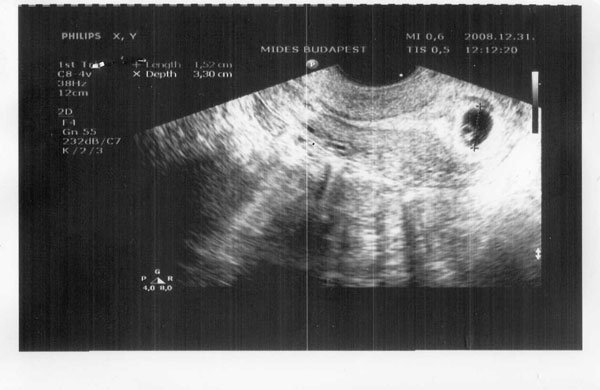

pocisan

pocisan

_ [/img]

_ [/img]